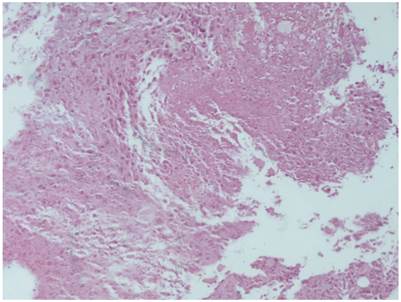

Figure 13

Cisplatin plus lipiodol group with HE X 100

Figure 14

Cisplatin plus microwave group; a) HE X 100, b) HE X 200